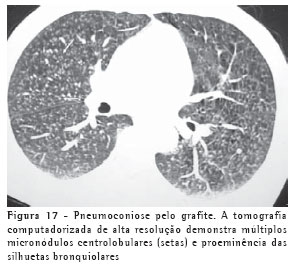

ASPECTOS DE IMAGEM DE OUTRAS DOENÇAS RESPIRATÓRIAS AMBIENTAIS E OCUPACIONAISAlém da sílica e do asbesto, outros agentes podem ser causadores de doenças respiratórias ambientais e ocupacionais. Na pneumoconiose pelo grafite, os achados tomográficos mais comuns são micronódulos pulmonares, espessamentos septais e opacidades parenquimatosas (Figura 17).(23)